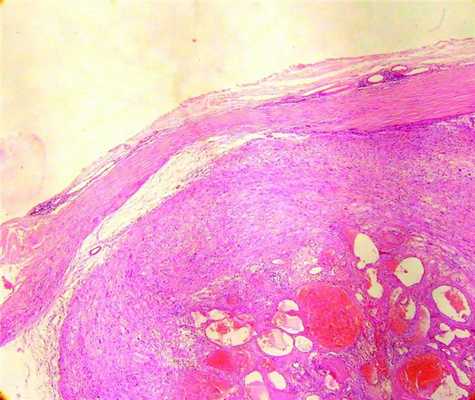

При микроскопическом исследовании в предэкваториальной зоне выявлен узел опухоли, расположенный в хориоидее и переходящий на плоскую часть цилиарного тела, отслаивая и инфильтрируя ее (рис. 1, а). Рисунок 1. Рис. 1а. Гистологическая картина увеальной шванномы. Опухоль локализуется в хориоидее и распространяется на плоскую часть цилиарного тела, отслаивая ее. Окраска гематоксилином и эозином. Ув. 40.

Опухоль представлена переплетающимися пучками рыхло расположенных клеток с округлым или вытянутой формы ядром, местами образующих ритмичные палисадообразные структуры, завихрения, тельца Верокаи (см. рис. 1, б). Рисунок 1. Рис. 1б. Гистологическая картина увеальной шванномы. Морфологическое строение опухоли. Окраска гематоксилином и эозином. Ув. 100. В центральном отделе опухоли имелся очаг ангиоматоза со старыми кровоизлияниями, очагами гиалиноза, небольшими внеклеточными отложениями гранул пигмента коричневого цвета (гемосидерин). Отмечена рассеянная лимфоцитарная инфильтрация. Довольно часто встречались крупные клетки с атипичными гиперхромными полиморфными ядрами. Митозы, некрозы отсутствовали. В области основания опухоли обнаружено резкое истончение склеры, участки ее разволокнения с формированием стафиломы (рис. 2). Рисунок 2. Рис. 2. Морфологическое строение стафиломы склеры. Окраска гематоксилином и эозином. Ув. 400. Выхода опухоли за пределы склеры в просмотренных срезах не было выявлено. Угол передней камеры был закрыт корнем радужки. Иридохрусталиковая диафрагма резко смещена кпереди.